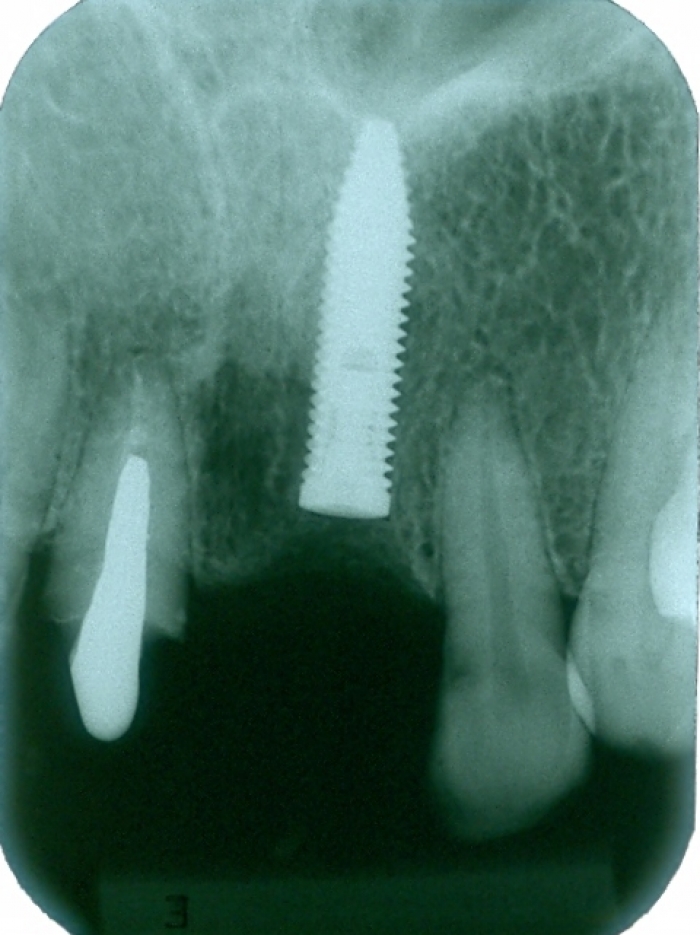

Imagens do caso inicial, com presença de fratura radicular do dente 21

Raio X inicial